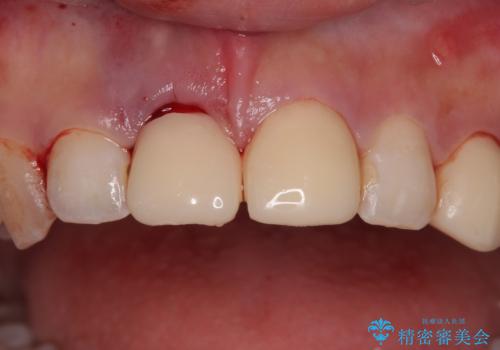

審美性を考慮し、仮歯を即日装着

抜歯を避けられない場合でも、「即日でインプラント治療+仮歯装着」により見た目を損なわないで治療を終えることができました。

抜歯をしてインプラントを埋入してから、4か月で最終補綴物(オールセラミッククラウン)の装着まで終えることができ非常に満足いただきました。